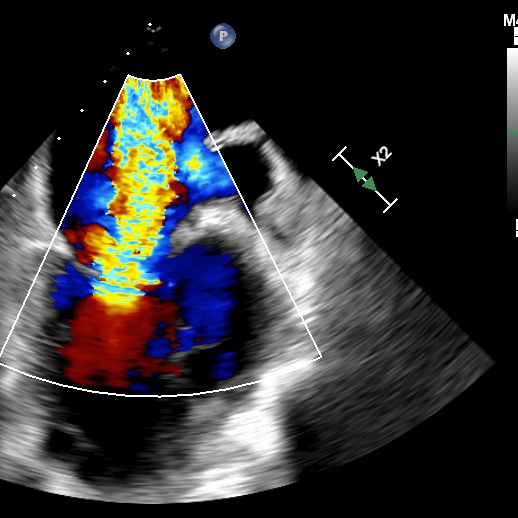

1.四腔心切面和二腔心切面可见左室高侧壁室壁瘤形成,二尖瓣瓣叶脱垂伴重度反流。

术后即刻超声提示二尖瓣反流下降至微量,二尖瓣平均跨瓣压2mmHg,多切面证实夹合组织充分,左上肺静脉多普勒波形由反向恢复正常。